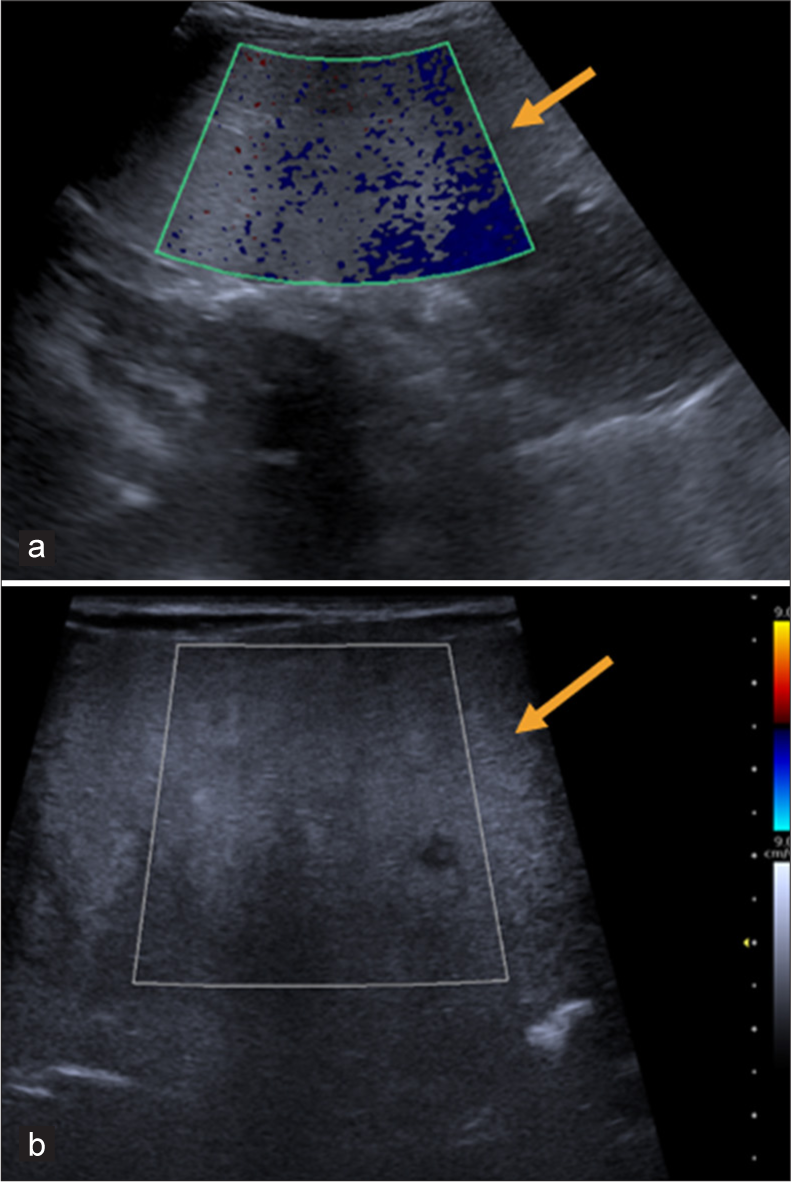

The patient’s basic laboratory parameters were within normal limits. Imaging evaluation at our institution began with an initial sonographic assessment of the abdomen, which revealed a large, homogeneous, hyperechoic mass occupying the abdominal cavity and exerting mass effect on adjacent structures [Figure 1].

On imaging, lipoblastoma, being a predominantly fat-containing solid mass, appears hyperechoic lesion on ultrasound, demonstrates low attenuation on CT, and appears hyperintense on T1-weighted and T2-weighted magnetic resonance imaging (MRI) sequences, with signal suppression on fat-suppressed sequences. Ultrasound serves as the primary imaging modality, and prior awareness of this entity can help prevent misdiagnosis. Cross-sectional imaging, including CT and MRI, is often required to evaluate the tumor’s internal characteristics and determine its extent.[6]

- A 1 year old boy with omental lipoblastoma. Ultrasound abdomen with (a) low frequency and (b) high frequency examination shows a large, predominantly hyperechoic solid lesion (orange arrows) occupying the entire abdominal cavity. (a) The bowel loops are seen displaced posterior to the mass.